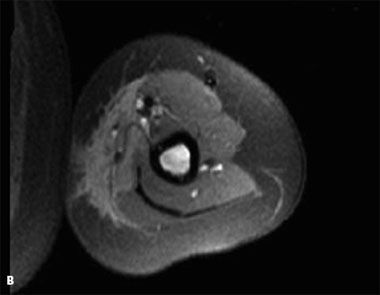

An MRI scan obtained 6 days   after therapy showed marked decreased   enhancement of the soft tissue   (B). On all sequences (T-1, T-1   fat-saturated, and fat-saturated with   contrast), the size of the mass had   decreased and normal muscle tissue   was visible. However, the bone marrow   signal was still abnormal, signifying   persistence of the infiltrative   process replacing the normal bone   marrow. This patient will continue to   receive close monitoring by the   hematology/oncology department.